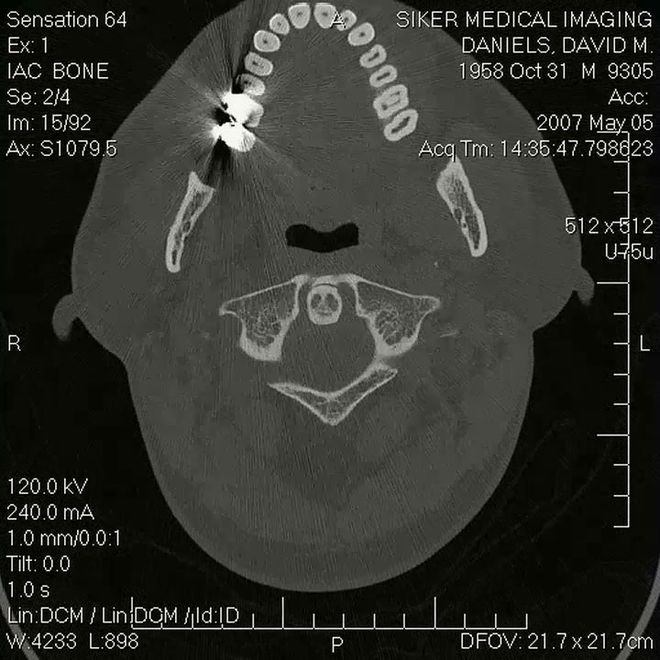

The mind of David Daniels by means of magnetic resonance imaging (MRI)

I have a family and I run a business. Family brings serious adult responsibility and so I sort of took the easy way out. I would love to do actual sculptures that use pottery clay or a form of plastic and create things that would sit on your coffee table or could be very large that are the motion sculptures themselves. I would never cut them up but would put some kind of magnetic filament into them and MRI the things and sell them as gallery pieces. You’re looking at time from the outside. That’s my gift – I see time from the outside and I see motion sculpture and see how the pieces all flow together and we’re a part of all that. So when you see these things as sculpted pieces from the side, that’s when they’re the most beautiful. Showing something that nobody sees is a revelation and an artistic triumph. My medium is a transitory puddle of goo (laughs), so you just can’t sell it.